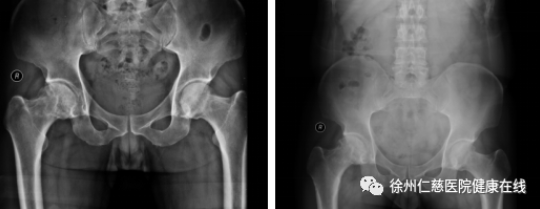

治疗前(左图)治疗后(右图)

39岁男性患者,双侧股骨头无菌性坏死,行体外冲击波+激光磁治疗,治疗后3个月双髋关节疼痛明显缓解,VAS:1-2分(治疗前6分),Harris:88分(治疗前23分)。

注:VAS指疼痛评分,Harris指髋关节功能